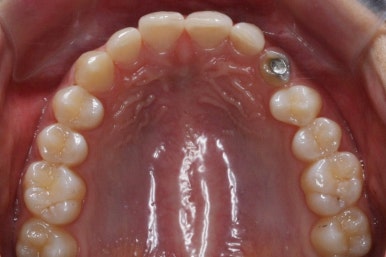

부산매복치아교정 키다리아저씨치과에서 소수술을 마친 모습입니다.

우선 남아있던 유치는 발치를 했고, 매복 송곳니에 장치를 붙인 후 잇몸 밖으로 체인 형식의 연장선만 빼놓았습니다. (두 개의 화살표 중 위쪽 화살표) 매복치아를 적절한 방향으로 요리조리 당겨줘야 하기 때문에 미니스크류를 이용했습니다. (두 개의 화살표 중 아래쪽 화살표)

수평으로 누워있었던 송곳니의 각도가 바로 잡힐 때까지는 계속 미니스크류만을 이용해서 당겨줍니다. 치아는 뼈속에서 헤엄치듯이 조금씩 방향을 잡아갑니다.

적절한 시기가 되면, 나머지 치아들을 가지런하게 할 준비를 합니다. 부산매복치아교정 키다리아저씨치과에서 이번에 사용한 장치는 클리피씨 입니다.